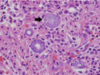

The wall of which cyst?

Periapical Cyst

Open clear areas = Cholesterol clefts where fat

used to be. Multinucleated cells (purple dots)

trying to break down cholesterol